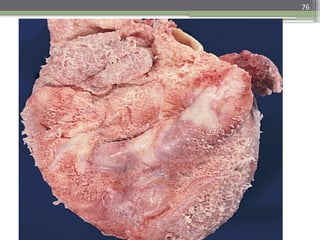

Complete rupture of a necrotic papillary muscle

76

75 Complete rupture ofa necrotic papillary muscle